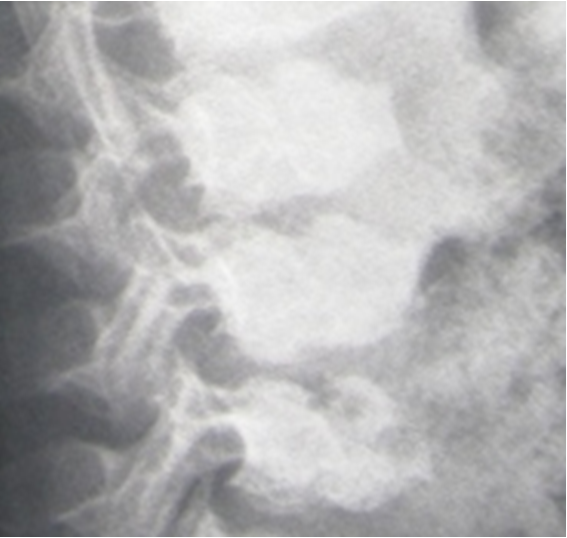

Figure 3: Lateral spine radiograph showed platyspondyly, double vertebral hump (beaked/wedged) vertebrae associated with irregular end-plates.